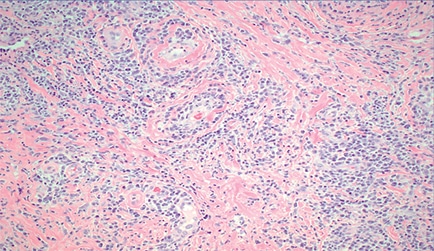

H&E sections from the perianal tags (Figs. 10 and 11) showed psoriasiform epidermal hyperplasia with superficial and deep perivascular and periadnexal chronic inflammatory infiltrate, Dr. Zenali explained.

Chronic inflammatory infiltrate is often lymphoplasmacytic with scattered histiocytes and eosinophils. Another histologic finding in syphilis is obliterative endarteritis, characterized by concentric endothelial swelling, fibroblastic thickening, and narrowing of the vascular lumen. Fig. 12 is a photomicrograph of Treponema pallidum immunostain highlighting the presence of spirochetes in the epithelium.

Microscopic examination raises a diagnosis of condyloma lata, which is distinct from the more commonly encountered anogenital condyloma (condyloma acuminatum). Condyloma lata occur in the setting of secondary syphilis. “On H&E alone,” Dr. Zenali said, “we cannot entirely exclude other venereal disease such as lymphogranuloma venereum [LGV] or granuloma inguinale [donovanosis], and immunostaining or silver impregnation methods can aid in further delineation.”